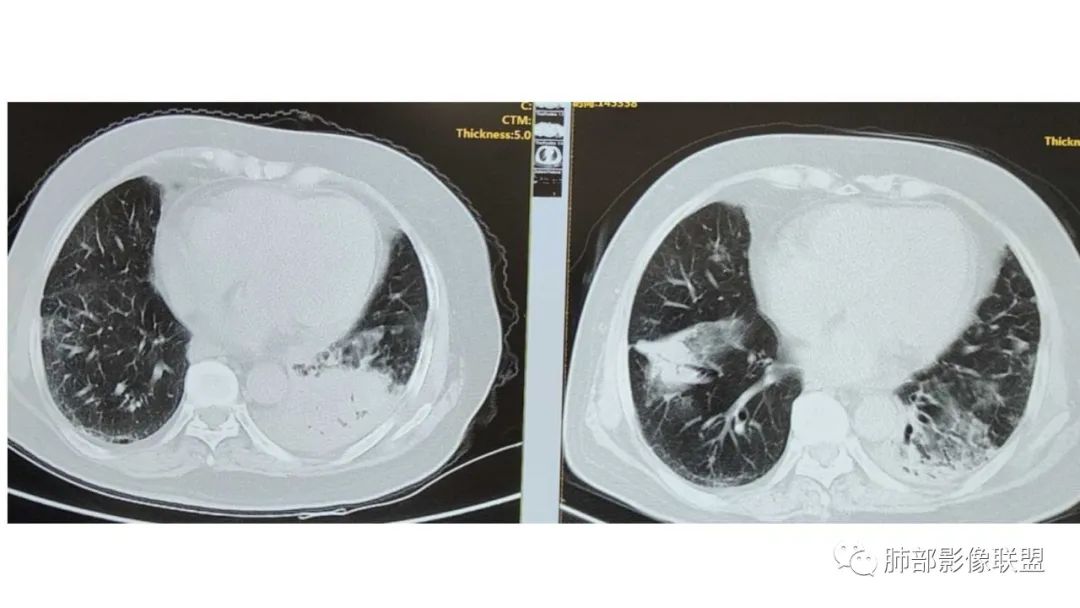

2、病灶常有一个主病灶,常位于下肺。后沿气道播散为多发病灶。

3、重力作用,叠瓦征。近叶间裂因重力效应,呈膨隆改变。

5、支气管粗细不均,呈“枯树枝征”,但与肺炎这一点鉴别不具有统计学差异。可发生支气管扩张

6、空腔形成,部分蜂窝状改变。